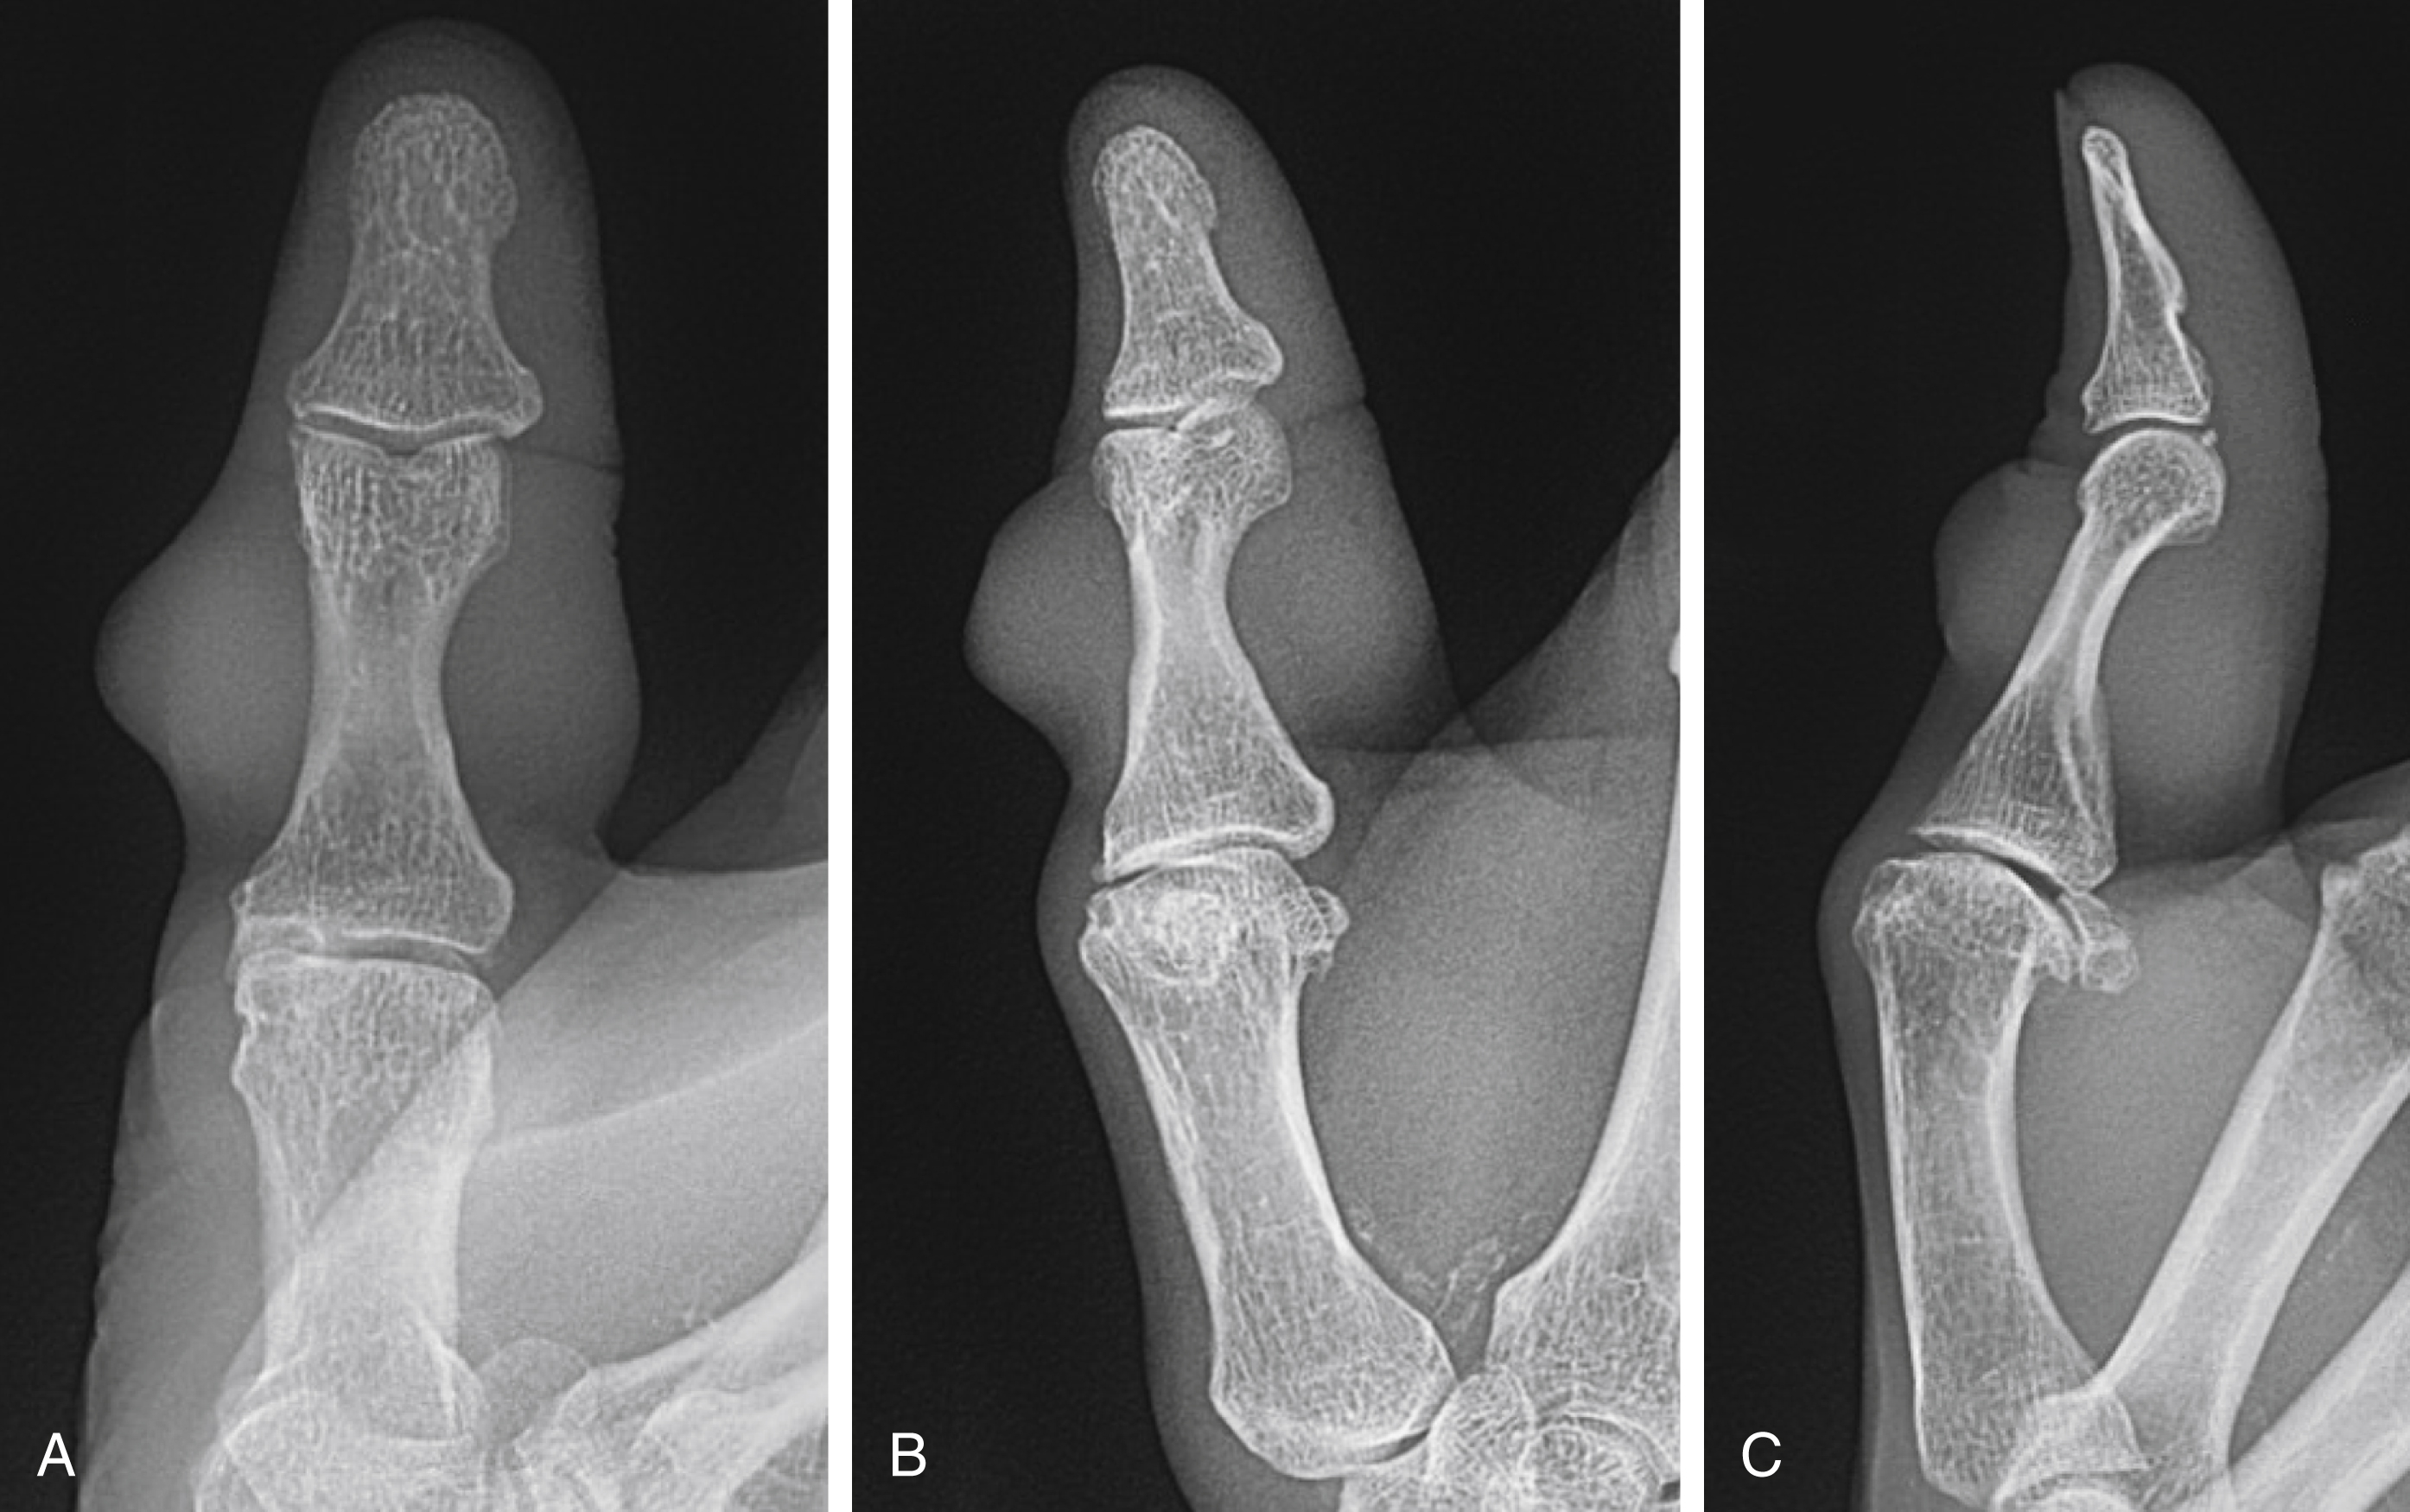

Plain radiographs are the mainstay of work-up for hand masses. The majority of soft tissue lesions will not be directly visualized, however radiographs can help diagnose underlying pathology causing soft tissue manifestations or demonstrate soft tissue calcification as well as distortion or erosion into the bone ( Fig. 60.2 ). Plain radiographs will demonstrate any primary osseous tumor. Well-circumscribed lesions are generally benign and slow-growing, while those that demonstrate periosteal reaction without signs of infection or trauma are worrisome for malignancy.

Mucous cysts typically present as a lesion on the dorsal distal phalanx proximal to the nail fold. Patients may complain of pain in the DIP joint as mucous cysts are associated with DIP joint arthritis. X-rays of the finger will often demonstrate dorsal osteophytes of the joint. Occasionally the only presenting symptom may be an abnormal nail plate when the cyst is located over the germinal matrix ( Fig. 60.7 ). When removing mucous cysts, excision of any associated osteophytes should be performed to prevent recurrence.